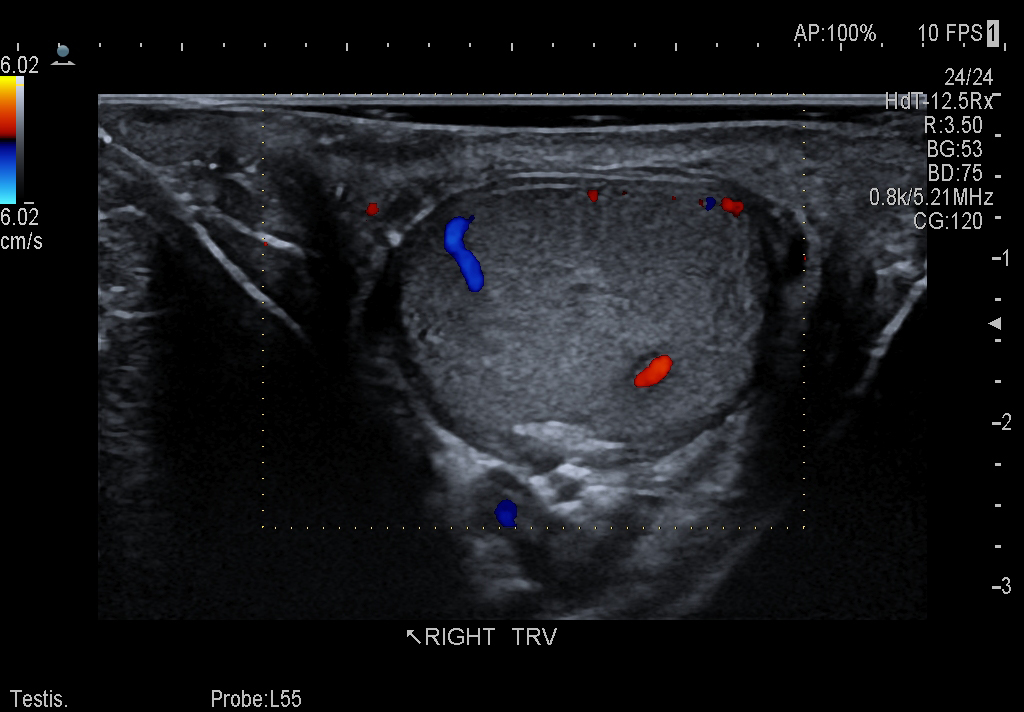

Testis Imaging using the L64 Transducer

Linear transducer that is ideal for scrotal and penile doppler imaging. Trapezoid Display extends field of view and enables visualization of entire structure.